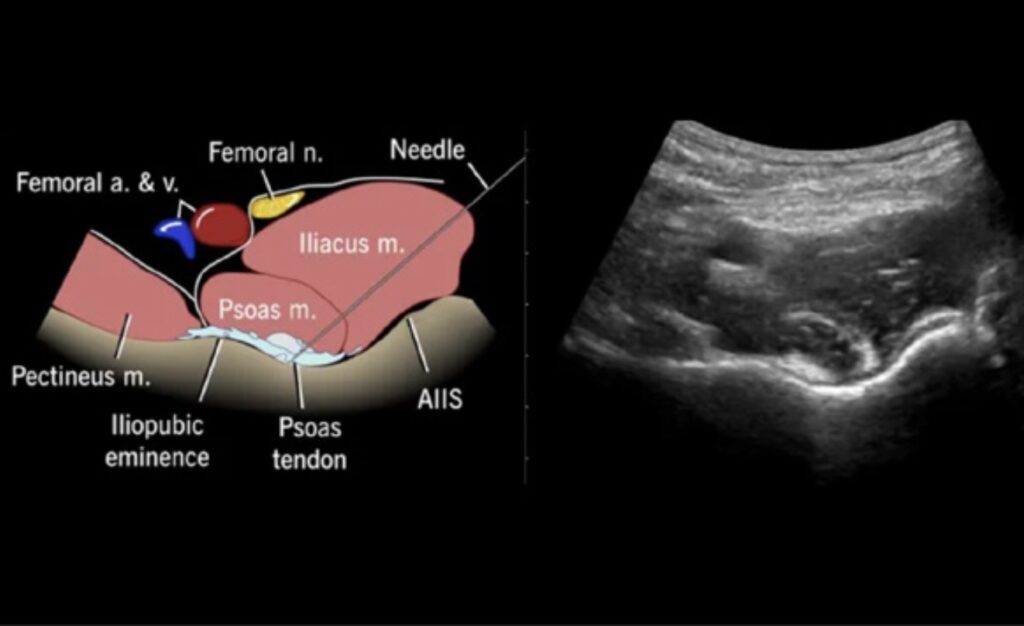

- Orient the ultrasound and patient to facilitate performance of the block (figure 1).

- Advance the needle under direct visualization to the psoas muscle. Use an in-plane approach, moving from lateral to medial until contact with the ilium is made under the psoas tendon (figures 3,4,5).

Figure 3. Illustration of the relevant anatomy for the PENG block. The femoral vein, artery and nerve are indicated by the blue, red and yellow circles, respectively.

Figure 5. Schema of correct needle placement, with needle tip under the psoas tendon demonstrating lift of the tendon with anesthetic administration (left). Ultrasound image with curved probe demonstrating the AIIS, psoas tendon and iliopubic eminence (right). AIIS, anterior inferior iliac spine.